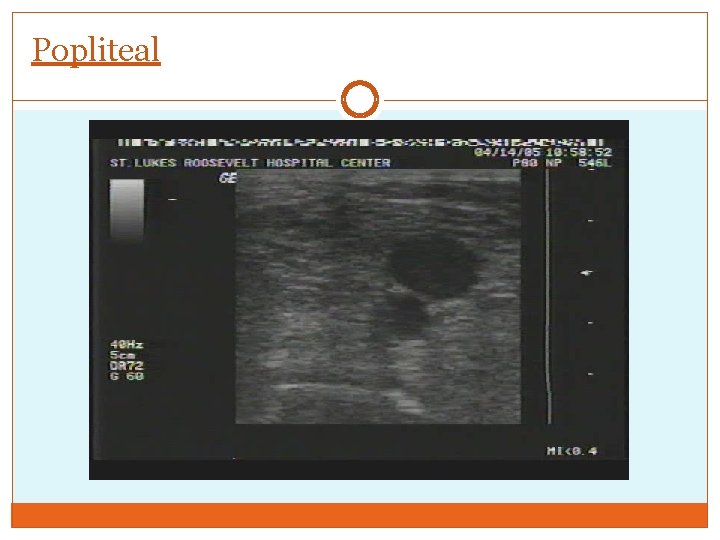

Popliteal Positioning Vein superficial to artery Scan to trifurcation point

Popliteal